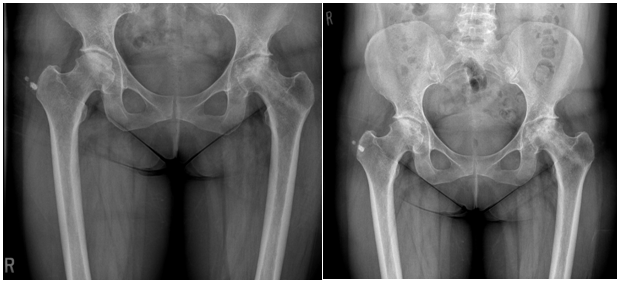

Immediate postoperative period was uneventful and the patient was mobilized non -weight bearing and was discharged on crutches. Subsequent follow up over the twelve month has been uneventful Figure 3.

She reported a marked improvement in her pain and function. In her clinic fellow up, x-ray (Figure 4) showed a slight deterioration from before, but there seems to be some consolidation and there has been no further collapse in view of her clinical presentation [Figure 5,6].

She did well for almost 18 months then she start to have pain in her left hip with limited activity. She underwent total hip replacement after 2 years from core decompression. Intra operative finding showed mild flattening of femoral head at weight bearing area without significant collapse [Figure 7,8].